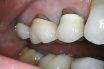

An artificial “cap” to replace the natural crown of a tooth, the enamel-coated part above the gum. Crowns are used when a tooth’s natural crown has been damaged beyond repair but also for cosmetic reasons, as when a tooth turns grayish after root canal therapy. Crowns in the front of the mouth are normally made of porcelain or other materials that can be matched in shade to the surrounding natural teeth; crowns on the grinding teeth—bicuspids and especially molars—are made of an alloy of gold or other metal, or at least have metal on the upper surface, for strength. In recent decades, dentists have developed several alternatives for cosmetic use when the crown of the tooth is intact.

A prosthetic restoration that reproduces the entire surface anatomy of the visible natural crown of a tooth. It may be partial (covering three or more surfaces of a tooth) or complete (covering all surfaces). It is made of gold or other metal, porcelain, or resin.

The upper portion of a tooth, which is safeguarded by enamel, is referred to as the crown. Additionally, a dental restoration known as a protective shell can be placed over a tooth, serving as a crown.